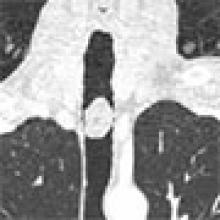

The patient is a 42-year-old male who presented to the emergency department with stridor. CT revealed a broad-based tumor 4 cm distal to the vocal cords and 7 cm proximal to the carina (Figure 1). The tumor was biopsied by bronchoscopy and pathology was suggestive of a schwannoma.